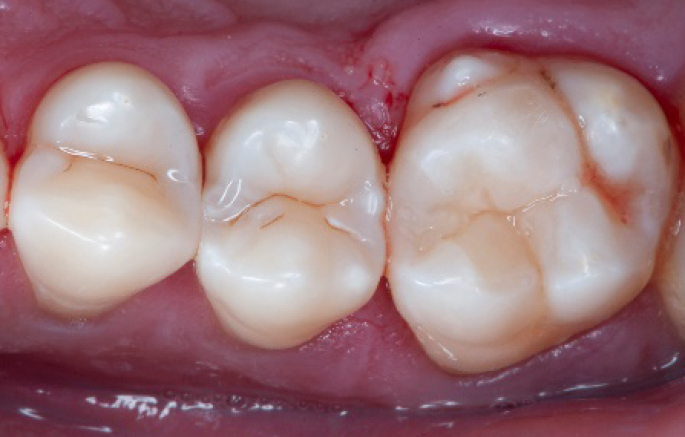

Final situation 2 weeks after the filling. Great comfort and no sensitivity at all were reported by the patient.

The situation after rubber dam removal.

Step 13:

Occlusal check

Step 14:

2 weeks control